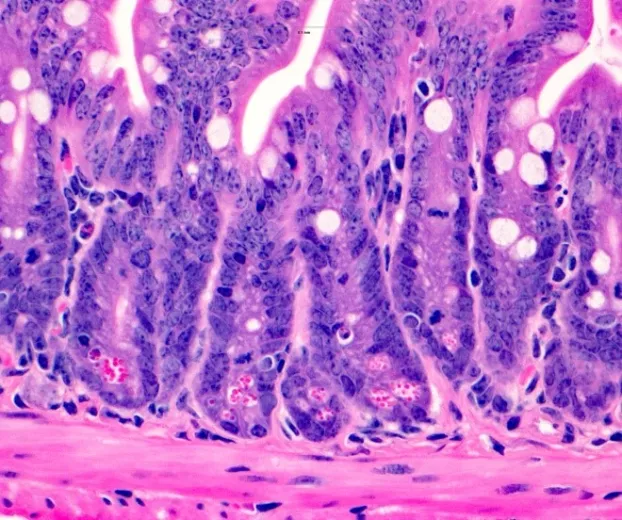

However the causal implication of these microbes in disease onset is not known. In this work we inoculated recipient germ free mice with stool from donor initially healthy that later develop CD (pre-CD), as well as matched individual that remained healthy (HC) during the same period of time.

Our analysis showed that pre-CD microbiota increased levels of fecal lipocalin-2 (a marker of gut inflammation) compared to mice receiving stool from HC. This study suggests that a pre-CD microbiota promote gut inflammation. This study will led to new therapeutic opportunity to prevent the onset of disease by targeting causal microbiome involved in the onset of Crohn’s disease